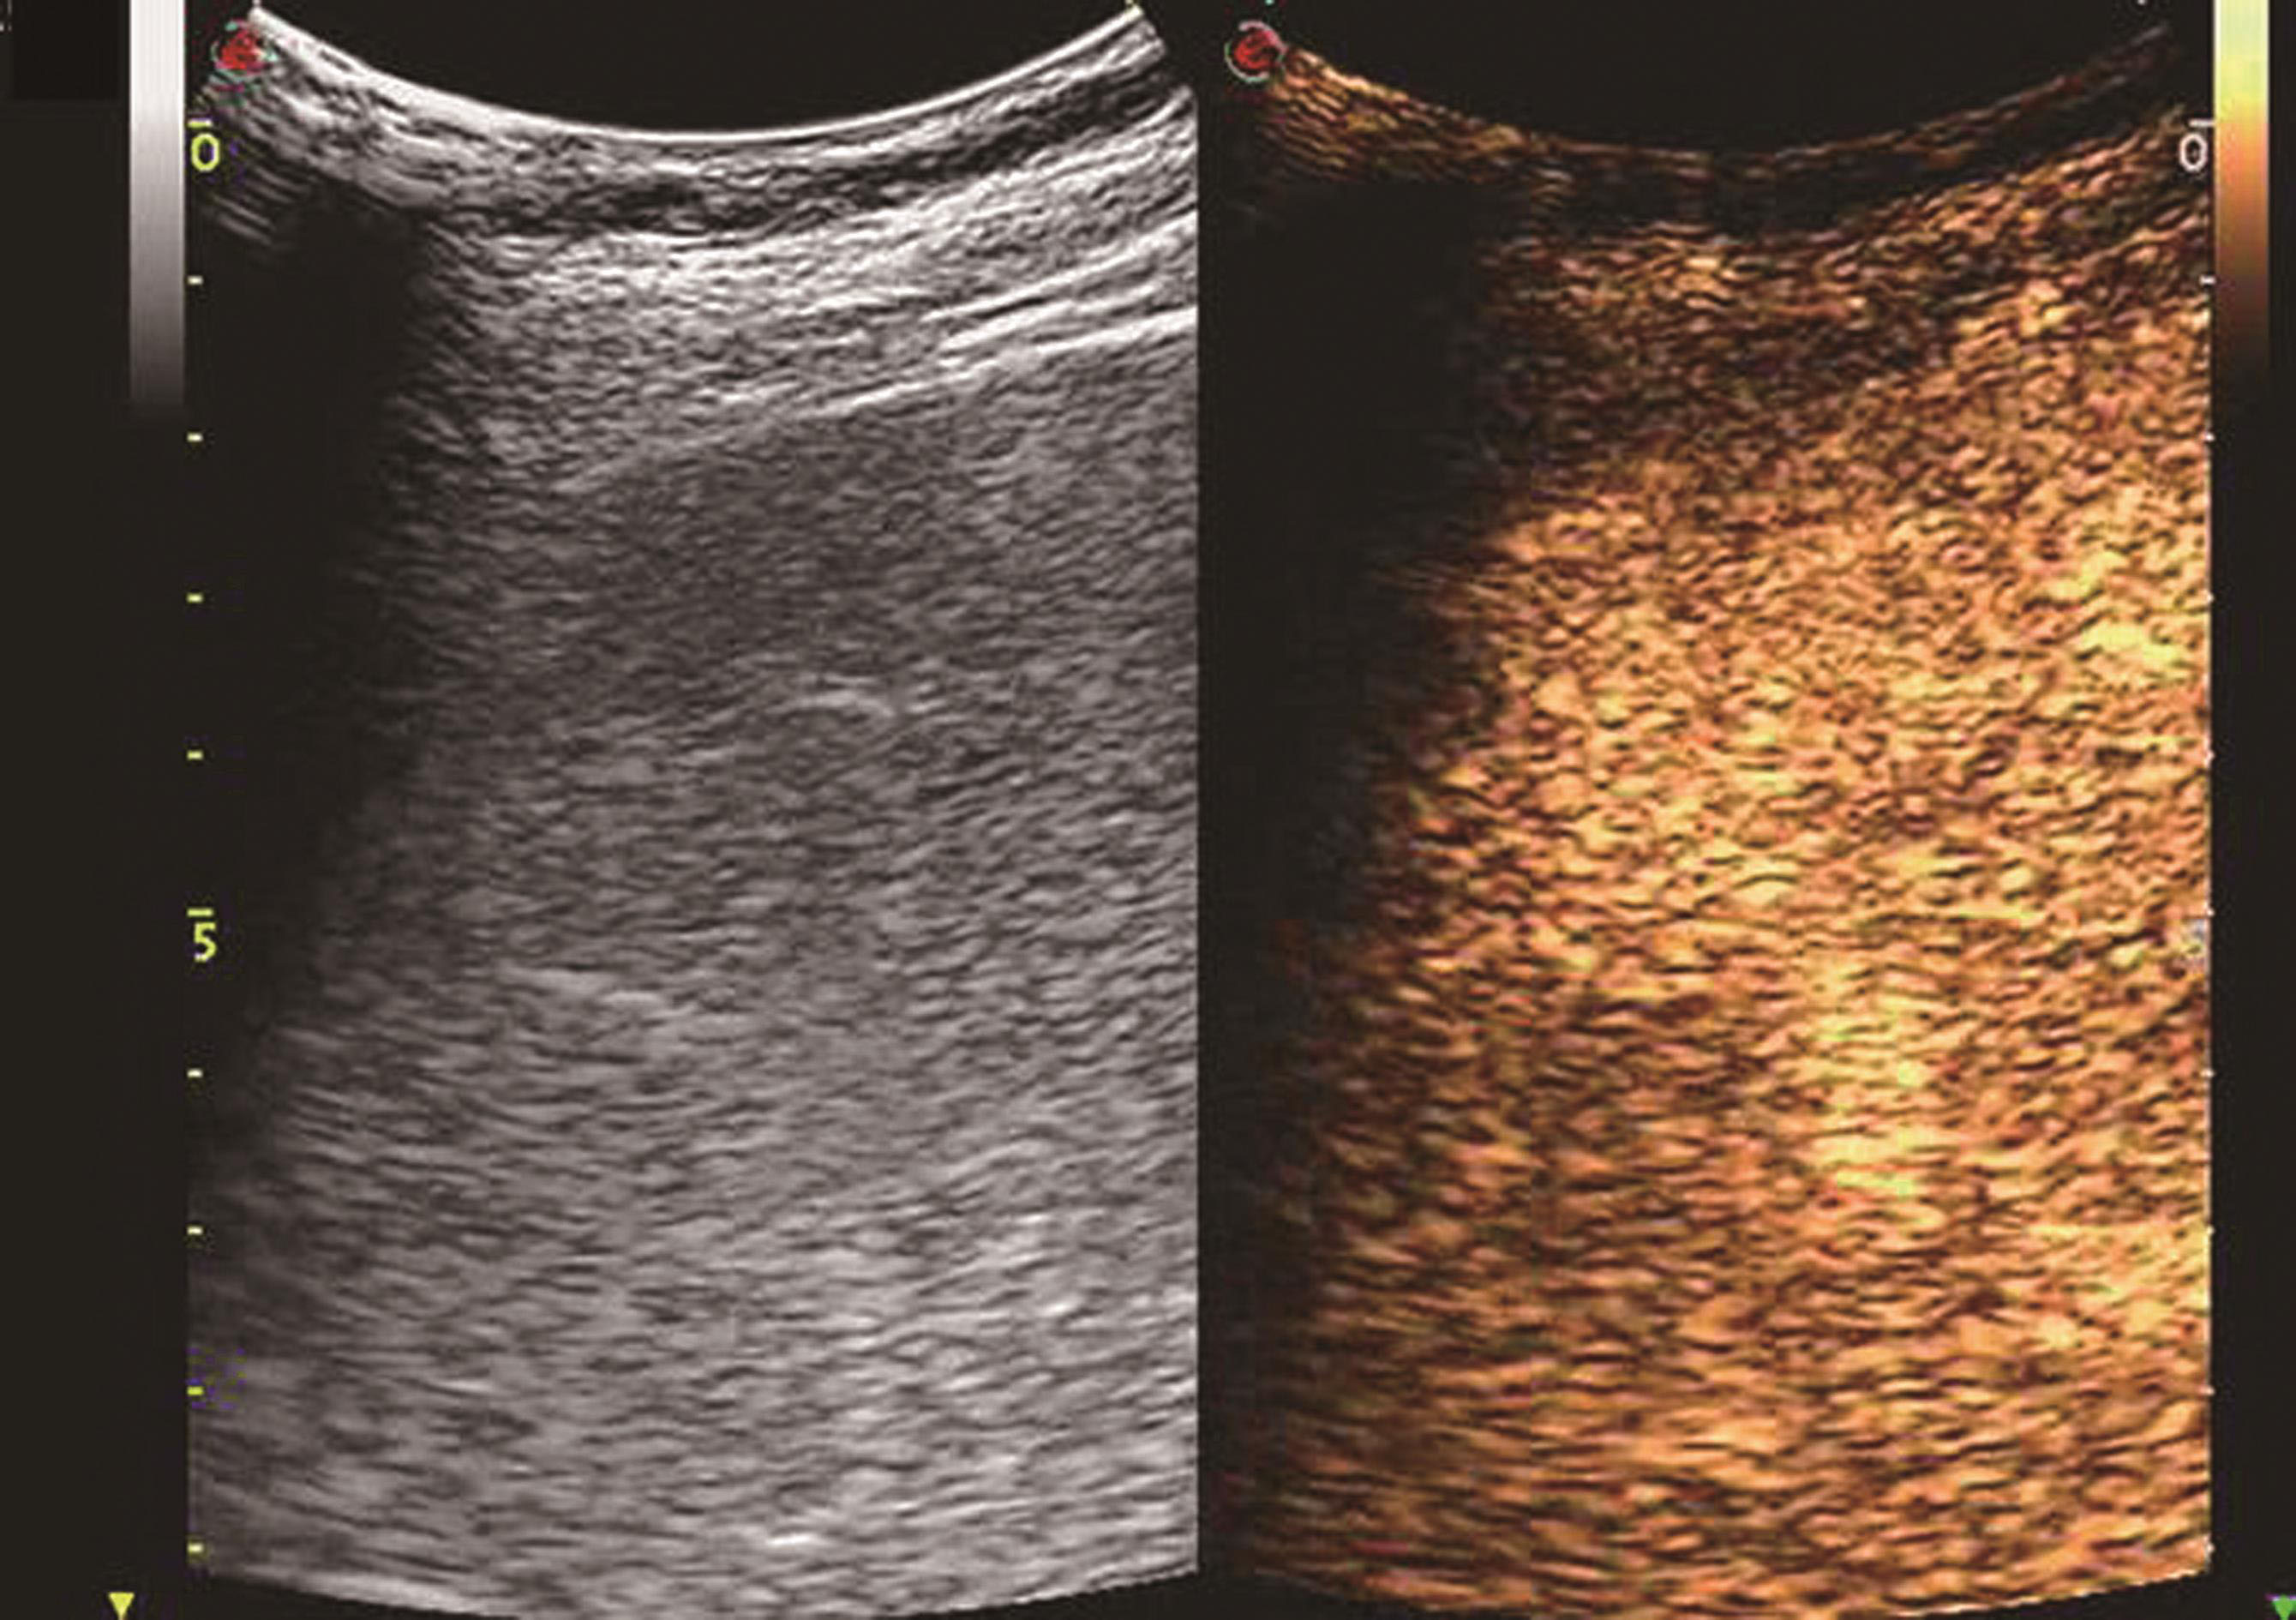

采用灰度调制显示(brightness modulation display)声束扫查人体解剖切面产生的图像,简称B超。其原理是超声仪器发射脉冲超声进入人体,然后接收各层组织界面的回声和脏器内部散射回声,并将回声脉冲电信号放大后送到显示器,构成二维断面图像,通过对超声图像断面的分析做出诊断。不同的组织有不同的声衰减和声阻抗,因此产生不同的回波强度,从而在显示器上显示不同灰阶强度的图像,利用这些回波来传达人体组织和脏器解剖形态和结构方面的信息。二维灰阶成像是超声在临床诊断中最基本和最常规的诊断模式,彩色多普勒血流成像(color Doppler flow imaging,CDFI)、彩色多普勒能量图(color Doppler energy,CDE)或其他血流图、三维超声成像(3-dimensional ultrasound,3-D US)、超声造影(contrast enhanced ultrasound,CEUS)、介入性超声治疗(interventional ultrasound,IUS)以及高强度聚焦超声(high-intensity focused ultrasound,HIFU)等超声诊断和治疗技术都必须建立在二维灰阶成像的基础上。因此,二维灰阶图像质量的好坏直接影响其他图像的质量。对肝脏检查而言,常规检查使用实时B超仪,凸阵或线阵探头,频率2.5~5.0MHz,根据不同的体形和病情进行相应的调节。